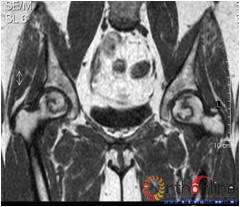

图1 女,22岁,(1)双侧股骨头坏死右侧B型,左侧C1型;(2)打压植骨术(加入BMP2)后5年,CT显示植骨生长良好,关节功能正常(Harris评分96分);(3)术后7年关节功能维持正常,股骨头维持正常外形

图2 男,22岁,激素性骨坏死,(1)双侧股骨头骨髓水肿,ARCO分期Ⅲa期,C3型;(2)X线片示股骨头塌陷,术前关节功能差(Harris评分50分);(3)打压植骨术(未加BMP2)后7年,关节功能好(Harris评分90分),股骨头有轻度塌陷,但头臼匹配好;(4)蛙式位显示股骨头臼匹配好